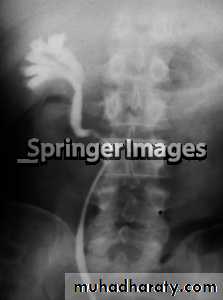

IVU :

- There is rounded or elliptical dilatation of lower end of ureter with thin lineal filling defect around it , resembling (cobra head appearance),

- Proximal dilatation of rest of ureter .

- In advanced cases hydronephrosis .

- In obstructed ureterocele , filling defect in the bladder